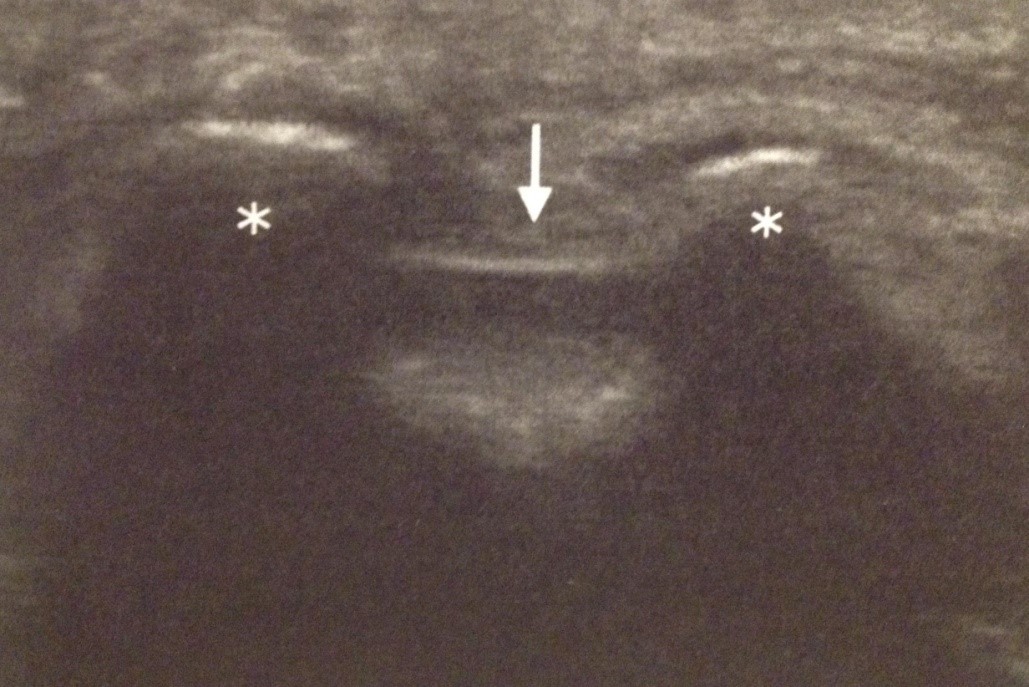

En la radioscopia, nos basamos sobre todo en los relieves óseos y las sombras y relaciones con estructuras radiotransparentes lo que limita su utilidad en patologías de partes blandas. La ecografía es especialmente eficaz en partes blandas, permite delimitar estructuras, sus límites y sus diferentes texturas, grasa, músculo, fascia, o con el Doppler las estructuras vasculares y su flujo.

Los nuevos ecógrafos aportan mayor resolución a las imágenes haciendo fácil distinguir, músculos, nervios, tendones y seguir sus trayectos completos lo que permite, a veces el diagnóstico en estructuras distales siguiéndolas en sentido ascendente hasta su origen (por ejemplo, en amputaciones, quemados, etc.).

La ecografía permite realizar casi todos los procedimientos que ya realizábamos con radioscopia, pero permite además, abordajes como los bloqueos interfasciales, siguiendo las fascias de músculos como el serrato, o el transverso y generar un efecto que recorre los compartimentos faciales de varios grupos musculares y ampliar la zona de acción más allá del sitio de punción, con áreas de distribución distintas de las metámeras tradicionales empleadas en la justificación de los bloqueos nerviosos.